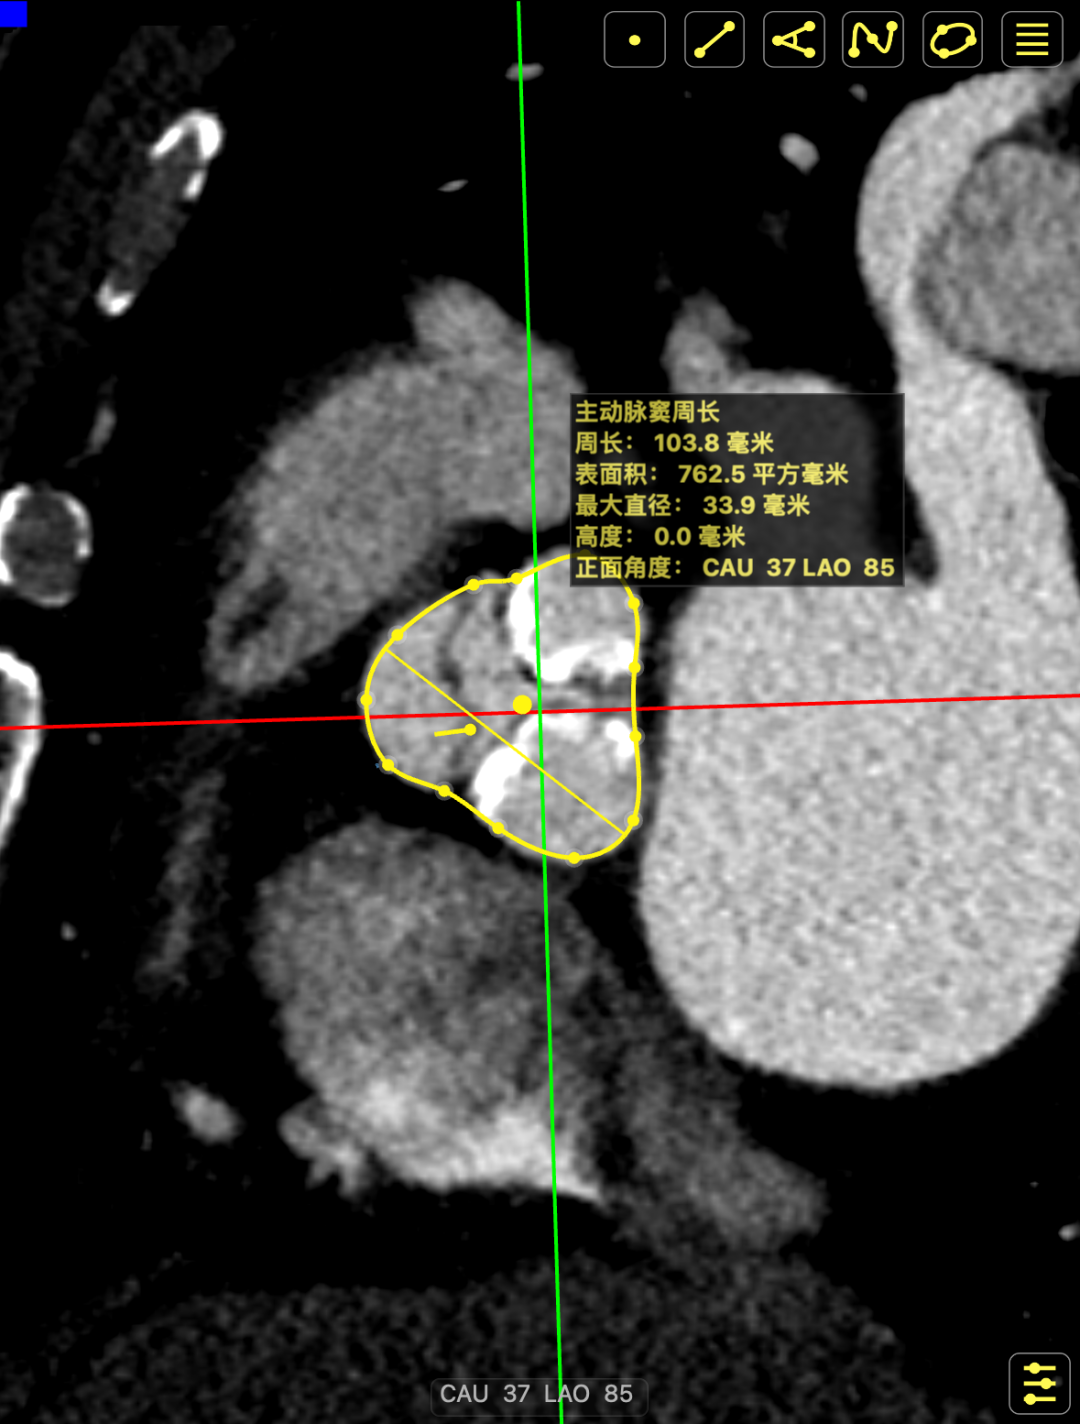

CT影像

CT影像